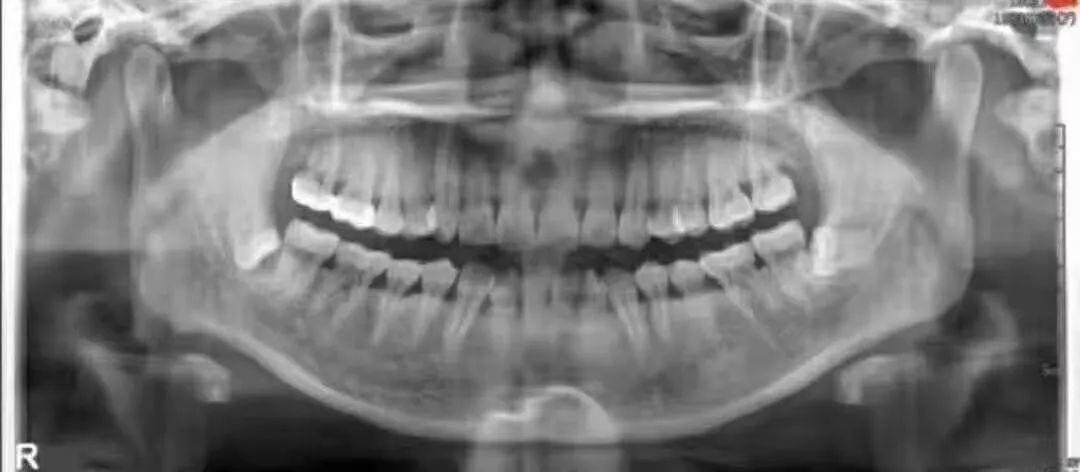

今天,這樣一組圖片在網(wǎng)絡(luò)上瘋傳——在圖片中,大致描述的是某患者在上海九院拔除智齒,兩顆智齒花費(fèi)了約21000元(消息真實(shí)性有待確認(rèn),畢竟材料費(fèi)、中藥費(fèi)比較讓人費(fèi)解)

其實(shí),類似的事件之前也有發(fā)生,據(jù)“北京北一”曾經(jīng)文章,之前在云南普洱,也發(fā)生過(guò)類似的事情,醫(yī)生給出的理由是

拔智齒收費(fèi)的標(biāo)準(zhǔn),首先智齒拔牙費(fèi)用是3000起,然后按距離下頜神經(jīng)管的距離依次加價(jià),4mm以外屬于正常范圍,每接近1mm加收2000,當(dāng)距離下頜神經(jīng)管距離在1mm范圍以內(nèi)時(shí),每增加0.2mm加收3500,傾斜度也是個(gè)問(wèn)題,首先考慮拔牙的就位道,就位道可以順暢取出智齒時(shí)不加價(jià),當(dāng)就位道不能順暢取出時(shí),根據(jù)難度加收1000~5000屬于正常收費(fèi)。以上標(biāo)準(zhǔn)不僅是牙醫(yī)們所應(yīng)該知道標(biāo)準(zhǔn),更是患者們更需要知道的標(biāo)準(zhǔn),試想這么大的風(fēng)險(xiǎn),萬(wàn)一我們失誤了,造成了醫(yī)療事故,是否患者們也只讓我們退費(fèi)呢?

真真假假,假假真真。智齒是否值上萬(wàn)元的價(jià)格,對(duì)這樣的事情,我們無(wú)法做出準(zhǔn)確的評(píng)估,還有待專業(yè)人士的評(píng)價(jià)。但毋庸置疑的一點(diǎn)是,拔除智齒,尤其是埋得深度較高,傾斜度不同,或者是下頜貼近神經(jīng)管的智齒,收費(fèi)程度肯定比普通拔牙要貴,這確實(shí)是真的